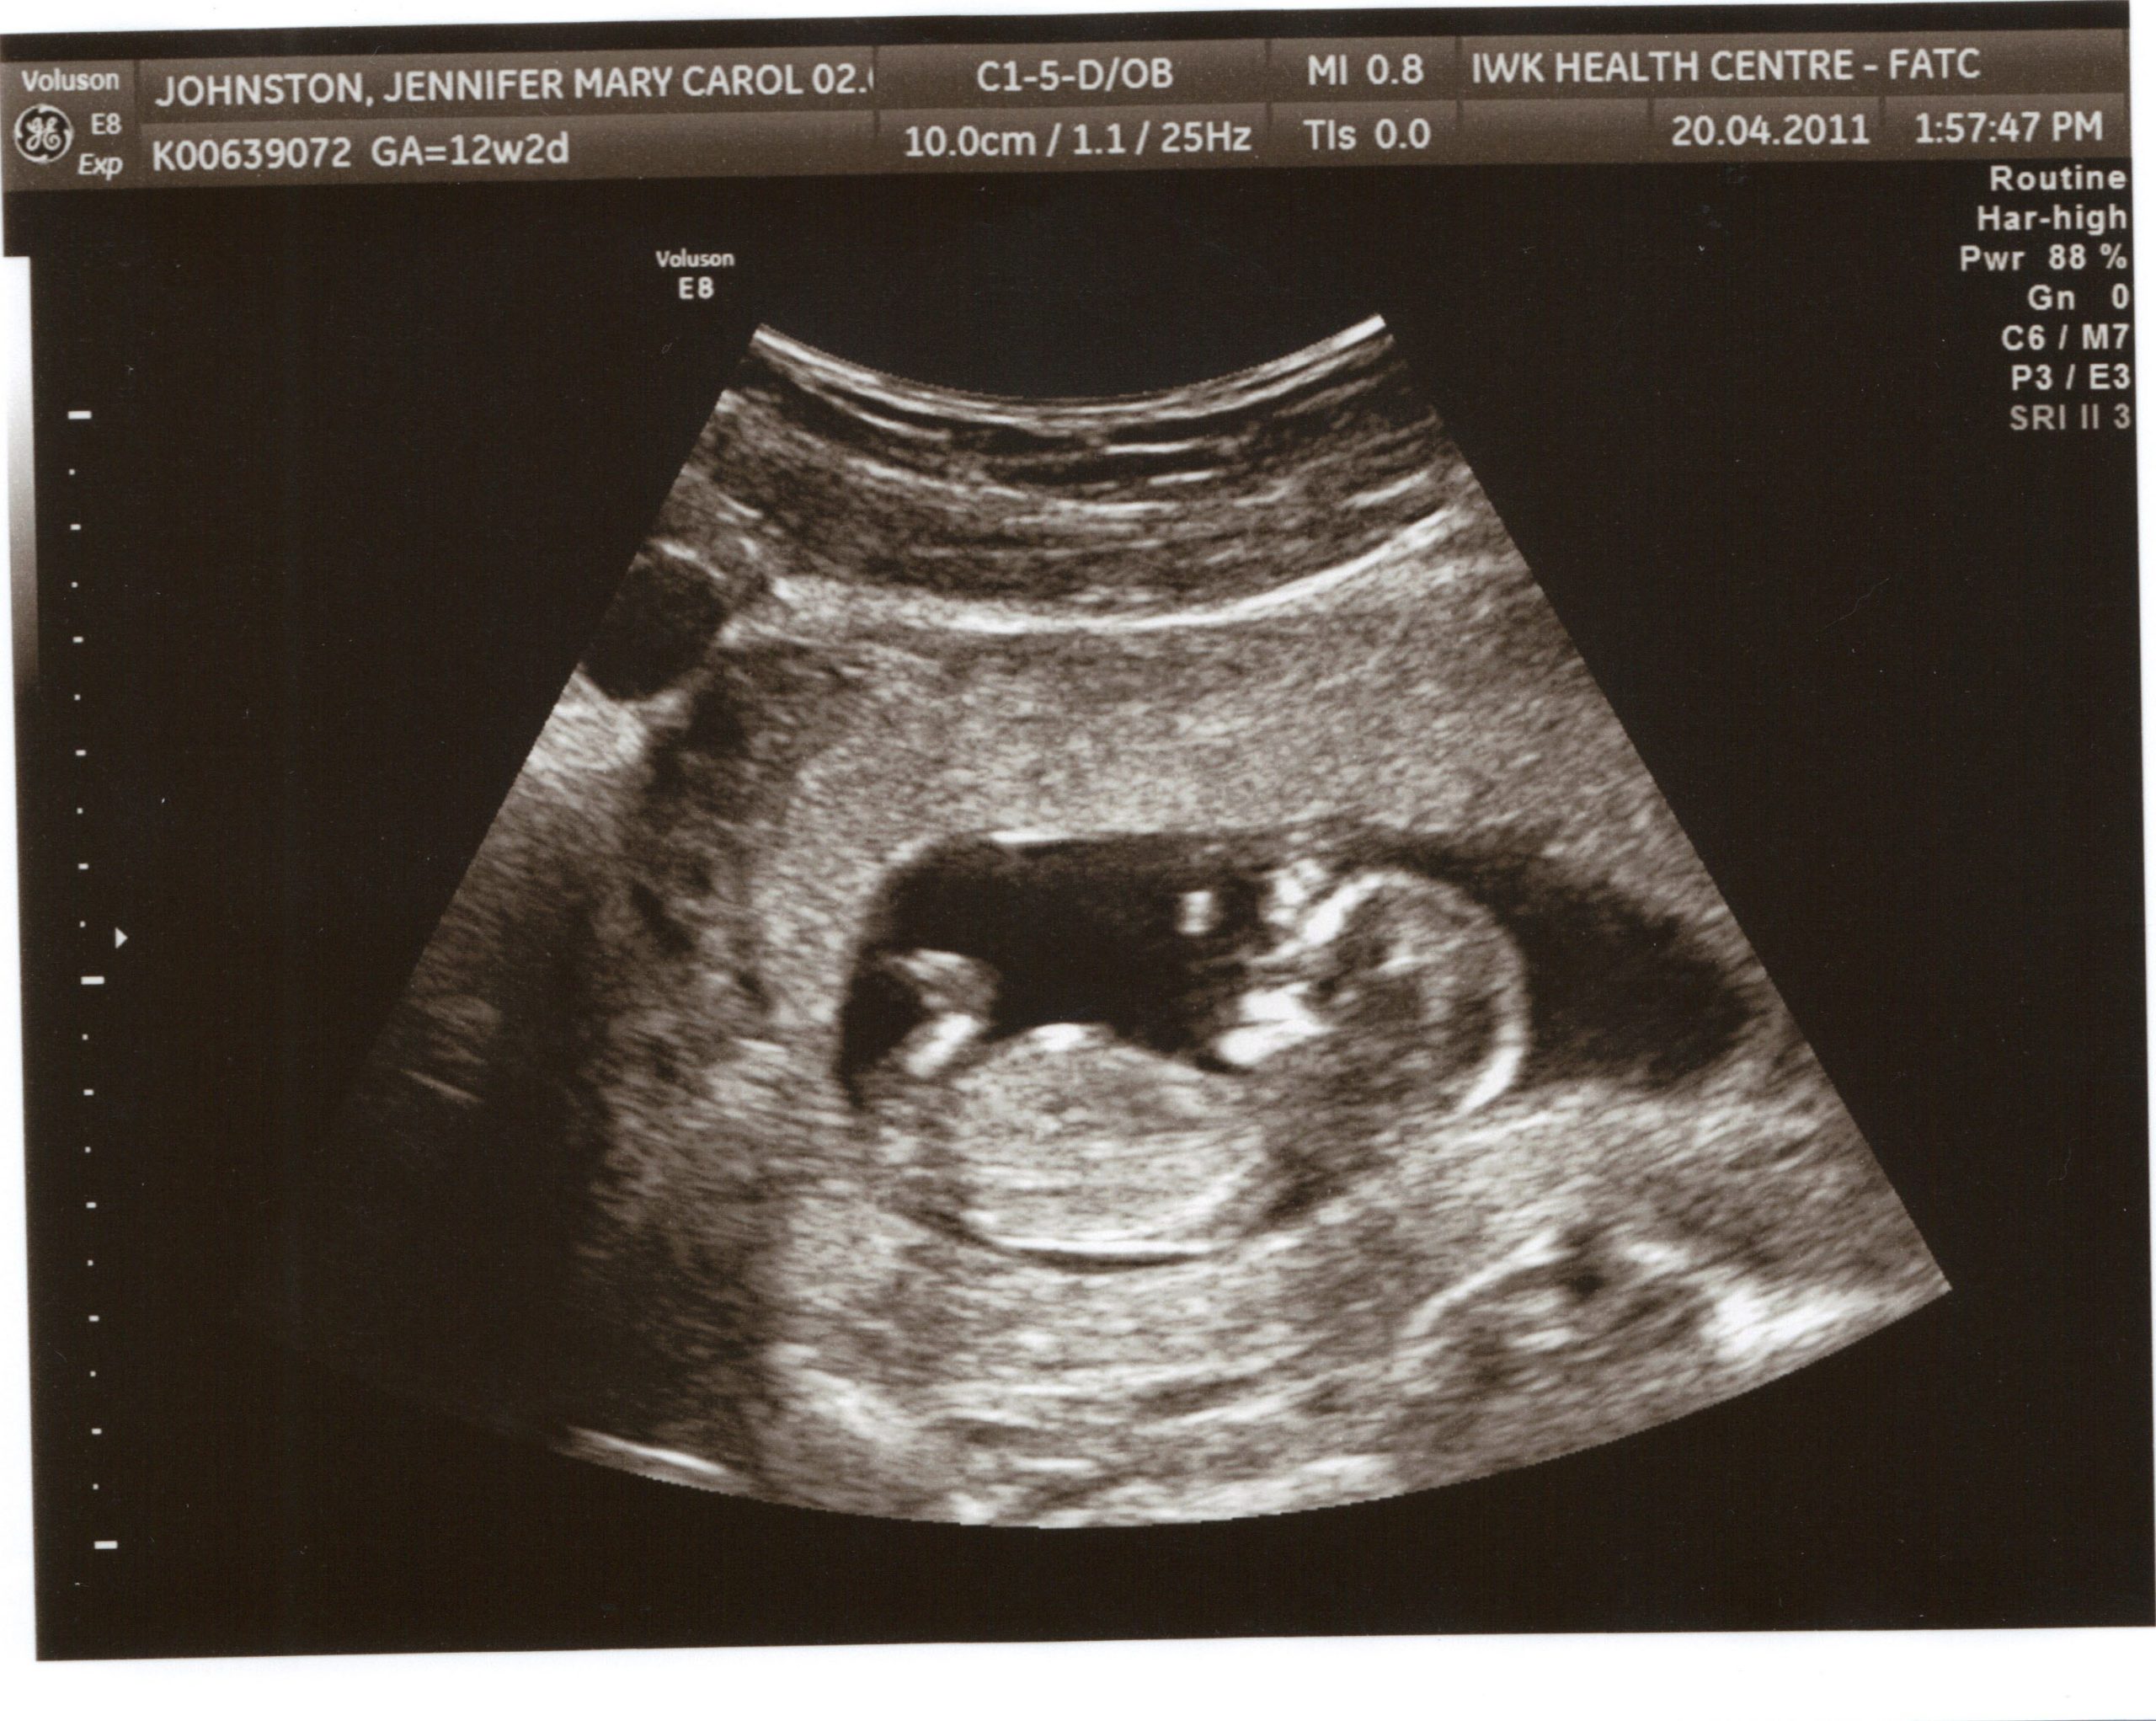

Ниже 12 недель беременности размер плода фото УЗИ:

На 12-й неделе беременности ваш малыш, вероятно, уже научился открывать и закрывать пальцы, сгибать пальцы ног, а также активно двигать руками и ногами. Он может проявлять рефлексы, включая рефлекс Моро, который также называют испугом. Если вы сделали УЗИ на 12-й неделе и слегка постучали по животу, вы сможете заметить, как ваш плод реагирует движениями.

С помощью ультразвукового исследования вы сможете увидеть своего малыша более четко, однако, если вас интересует пол ребенка, ваш врач не сможет с уверенностью это определить. (Вы можете пройти неинвазивное генетическое тестирование, чтобы узнать пол раньше.)

Ниже плод на 12-й неделе беременности фото:

Ниже представлено УЗИ на 12 неделе беременности: